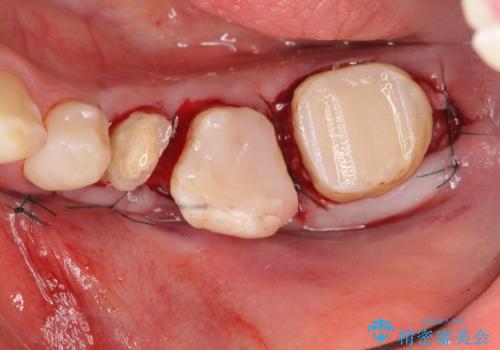

- 左下の奥歯がズキズキ痛むので診て欲しいといらっしゃった方の症例です。他院では5番目と7番目の歯を抜歯してインプラントと言われたが、出来れば歯を残したいとのことでした。

痛みの原因は6番目の虫歯であること、5番目、6番目の歯は歯茎より深い虫歯であり現状では保存が難しいことを説明した上で、歯を挺出させる部分矯正と歯茎を下げる歯周外科を行いました。

手術後歯茎の治癒を待ち、オールセラミッククラウンによる補綴を行いました。